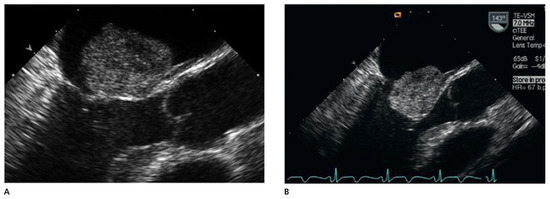

A patient with Morbus Behçet was admitted with severe symptomatic aortic regurgitation caused by aortitis that mimicked infective endocarditis. After aortic valve replacement and antibiotic treatment, regurgitation and systemic inflammation recurred....